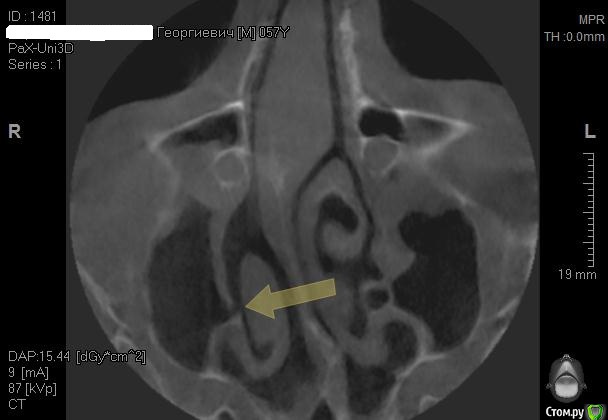

Kostoprav Опубликовано 26 апреля, 2015 Поделиться Опубликовано 26 апреля, 2015 Всем доброго времени суток коллеги!Проблема в следующем- высокая септа и мукоцеле на медиальной стенке пазухи.Мой план: сделать два окна в пазуху по обе стороны от перегородки, аккуратно попробовать отслоить слизистую и если получиться не порвать ее установить два болта не трогая кисту. В случае тотального разрыва мембраны спилить перегородку, убрать мукоцеле, зашить пазуху и повторно пойти на синуслифт через 2 месяца.Хотелось бы услышать Ваши варианты дорогие коллеги. 1 Ссылка на комментарий

Alexey Doc Опубликовано 28 апреля, 2015 Поделиться Опубликовано 28 апреля, 2015 При просмотре КТ еще обращаю внимание на состояние решетчатых воронок, зачастую при их окклюзии есть проблемы в пазухах.на картинке цифрой 3 обозначена. Если патологии не видите то по тактике согласен, если есть вопросы то консультация Лора 1 Ссылка на комментарий

Kostoprav Опубликовано 28 апреля, 2015 Автор Поделиться Опубликовано 28 апреля, 2015 (изменено) Пришлось пойти по варианту №2. слизистая пазухи в месте прикрепления к септе просто расползлась да так что в кучу не собрать. Спилил аккуратно перегородку, убрал мукоцеле (откачал с нее 2 мл. остальное убрал в месте с оболочкой зажимом), заштопал все герметично правда вот теперь думаю, правильно ли сделал что наглухо ушил, может дренаж оставить нужно было? Изменено 28 апреля, 2015 пользователем Kostoprav Ссылка на комментарий